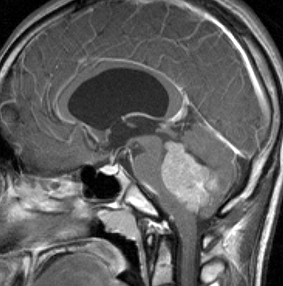

medulloblastoma with extensive nodullarity

2歳の子どもにできたmedulloblastoma with extensive nodullarityのMRI CISS image矢状断層。多数の結節に分かれるこのタイプの髄芽腫は3歳未満の小児に発生し,化学療法によく反応します(右は1コースのICE化学療法後の顕著な縮小を示します)。従って,classical medulloblastomaよりも予後が良いといえます。リスクを侵して全摘出する必要はなく,また幼児発生であることも考慮すれば放射線治療の intensityも高く設定する必要はないのかもしれません。同じ3歳未満のhigh-risk groupの髄芽腫といえども,2歳児のanaplastic medulloblastomaとは治療反応性に天地の開きがあります。